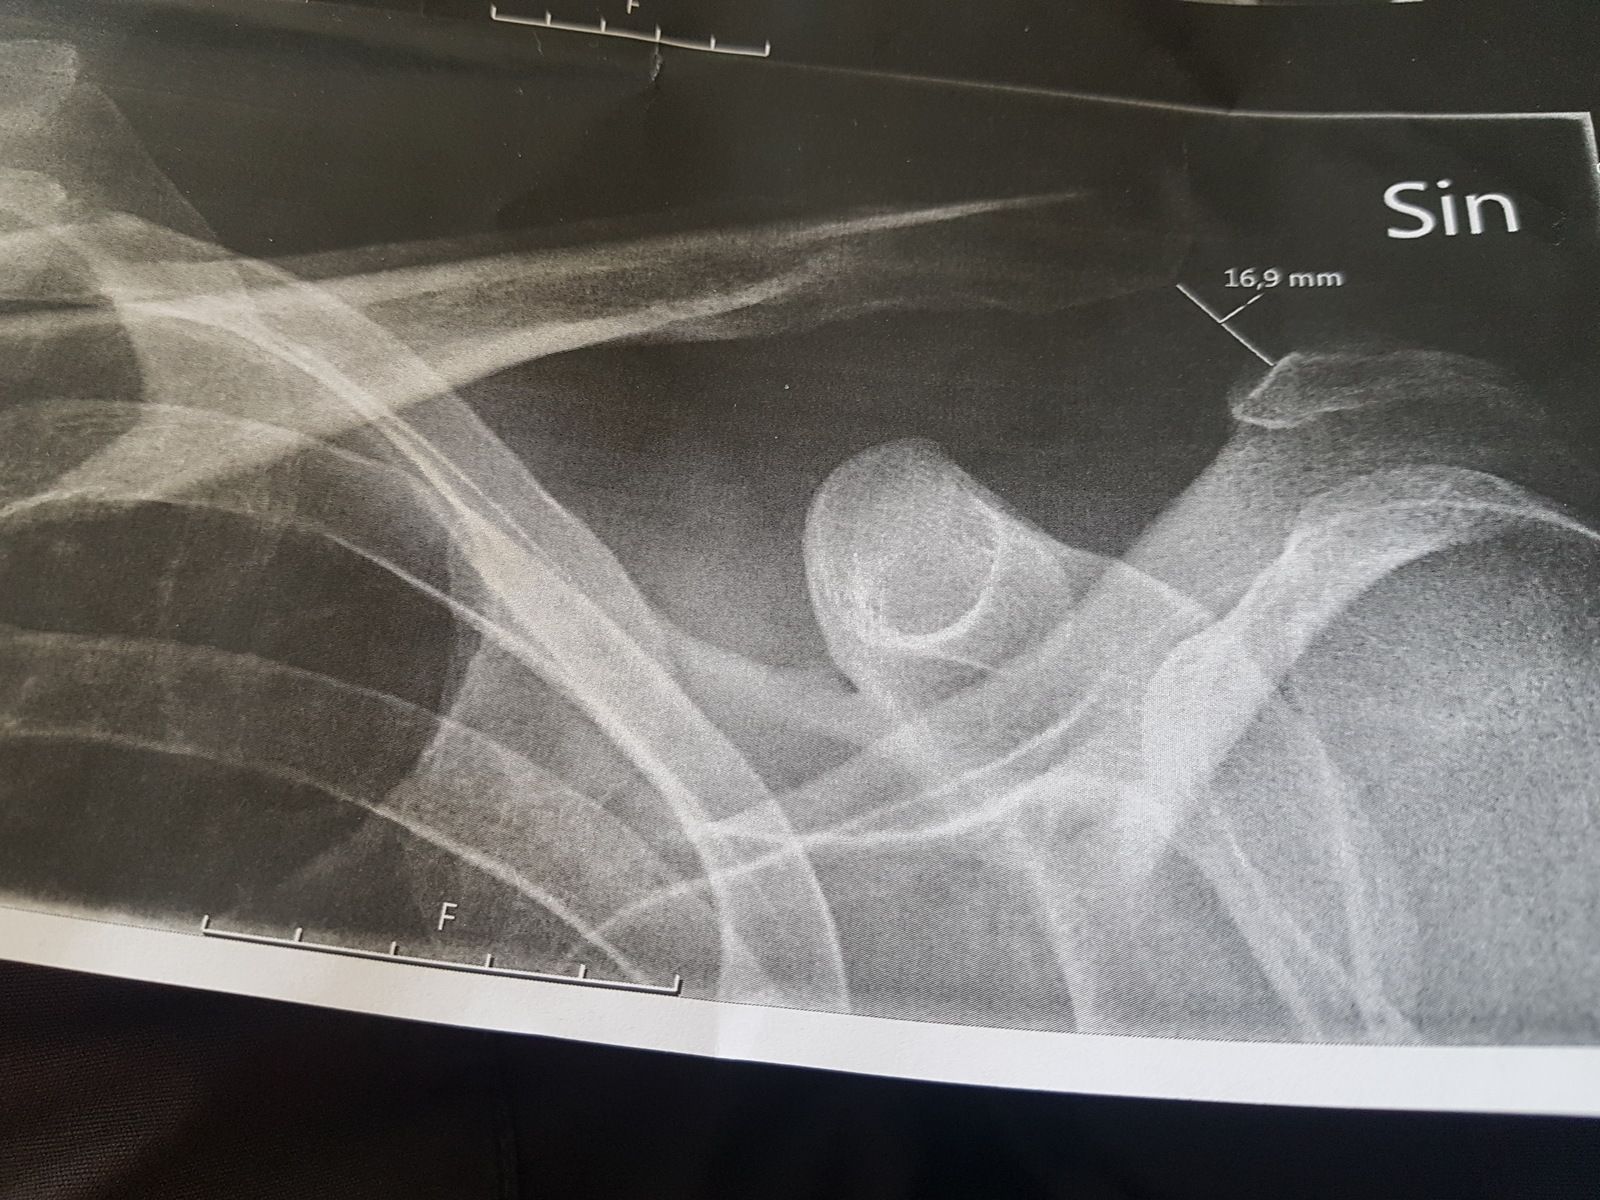

Tack för era tips å erfarenheter, har väldigt svårt att bestämma mej. Vore skönt att kunna ta en titt in i framtiden

Bilagor

• 20190705_160302.jpg

20190705_160302.jpg

302.2 KB · Besök: 818

Ac luxation , nyckelben ur led

MrMe sa:

Är benet av så tycker jag du ska få det opererat.